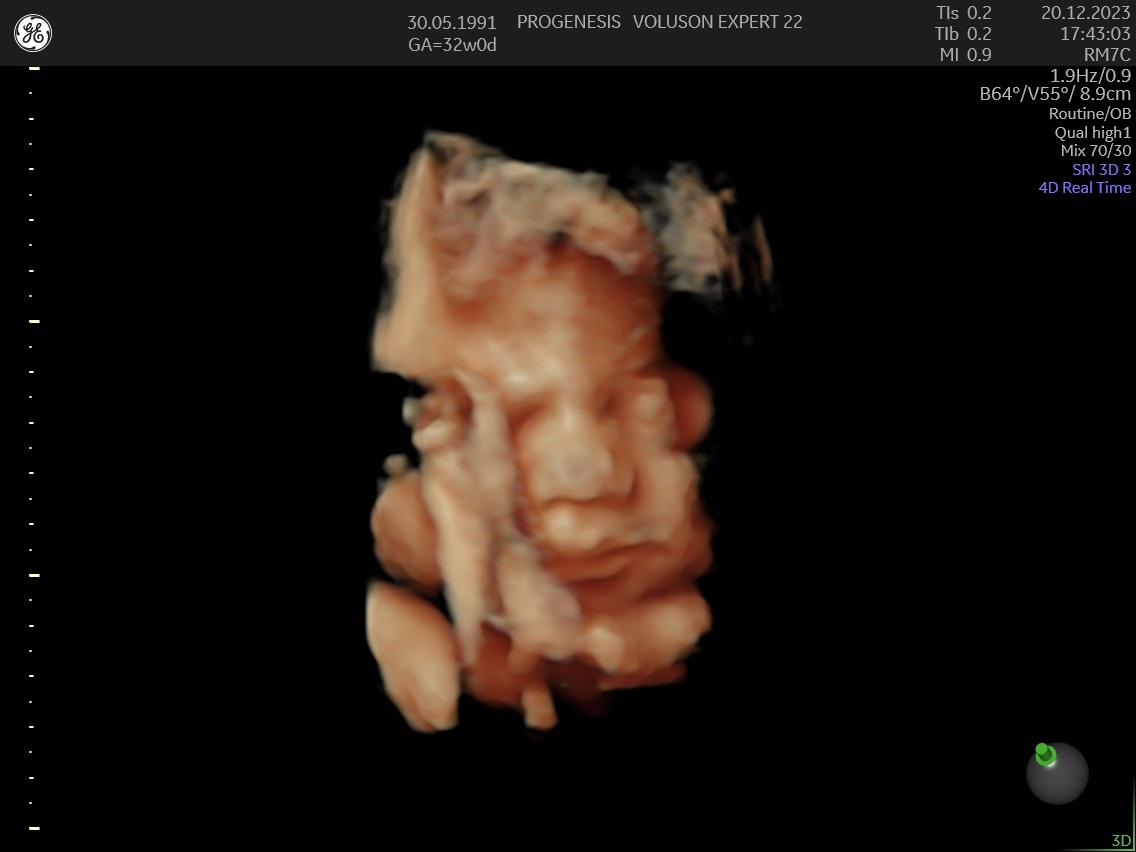

3D/4D LIVE Υπερηχογράφημα

Το 3D/4D LIVE είναι μια νέα τεχνολογία υπερήχων που δημιουργεί εικόνες του εμβρύου σε τρισδιάστατο ή τετραδιάστατο χώρο. Οι εικόνες αυτές είναι πιο ρεαλιστικές από τις παραδοσιακές εικόνες υπερήχων και δίνουν στους γονείς μια πιο ολοκληρωμένη εικόνα του μωρού τους.

Σε πιθανά ανατομικά προβλήματα του εμβρύου μπορούν να βοηθήσουν στην κατανόησή τους από τους γονείς.

Ωστόσο, οι εικόνες 3D/4D LIVE δεν μπορούν να αντικαταστήσουν τις παραδοσιακές εξετάσεις υπερήχων.